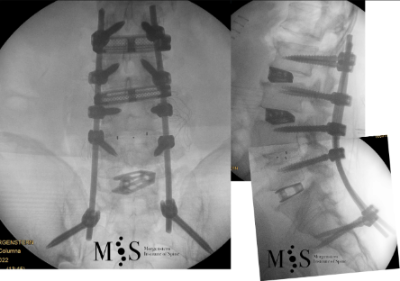

In these painful cases, surgery is indicated to (partially) correct the deformity and mainly to reduce/eliminate the pain generated by the scoliosis. In the most severe scoliosis cases an osteotomy (chiseling of a vertebral bone) may be required to straighten up the spine and reduce its deformity.

At the Morgenstern Institute of Spine we use the most advanced surgical endoscopic and percutaneous techniques to correct the degenerative scoliosis and speed up the patient’s recovery time. Hospital discharge is usually just a few days after surgery.